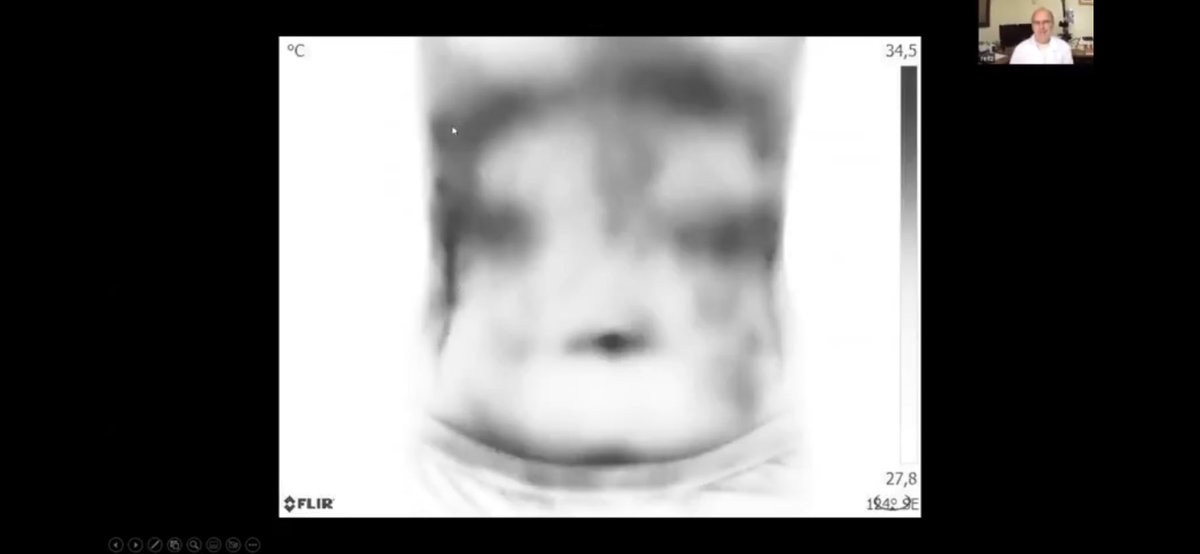

التصوير الحراري المحوسب وتحليل الدم الحي بعد حقن Covid-19.

آنا ماريا ميهالسيا ، دكتوراه في الطب ، تجري مقابلة مع د. فيليب ريتز ، عالم أحياء ، مخترع ، باحث طبي في البرازيل فيما يتعلق بالنتائج التي توصل إليها في C19 في الأشخاص الذين تم حقنهم، 1️⃣ t.me

بالتصوير الحراري المحوسب الذي يكشف عن تخثر الدم بدون أعراض في نظام الأوعية الدموية بأكمله وصور الدم الحية التي تظهر جزيئات أكسيد الجرافين النانوية و تشوهات الدم الأخرى.